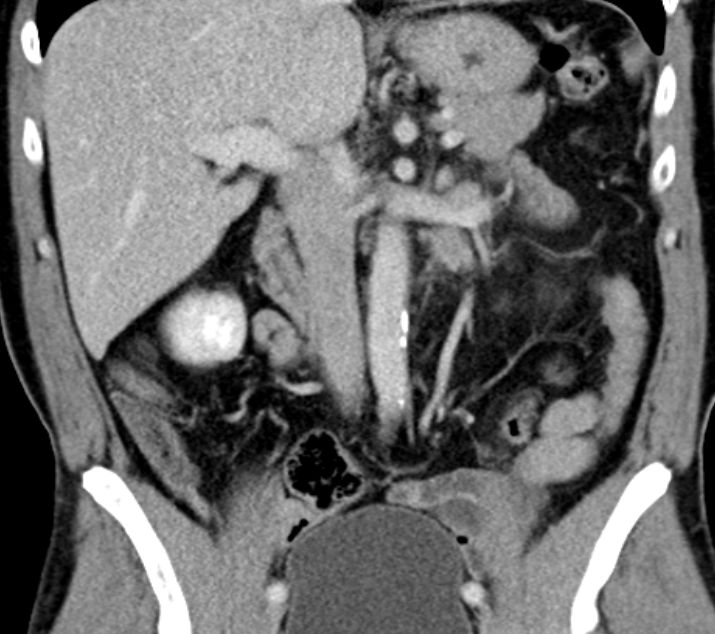

54-jähriger Mann mit

Rückenschmerzen. Bei der Durchuntersuchung wurde eine Metastase in BWK5 mit drohendem Querschnitt gefunden. Es erfolgte eine Laminektomie und Stabilisierung von Pedikelschrauben von T3,4 aud T6,7. Als Primärtumor wurde ein Nierentumor T3 pN2(4/5) m1oss gefunden. |

Histochemie: GATA 3 kräftige Kernfärbung. Zytokeratin 7, Zytokeratin färben Tumorzellen kräftig zytoplasmatisch.Zytokeratin 5/6 negativ. p40 färben einen Teil der Tumorzellkerne. Diagnose: invasives Urothelkarzinom des Nierenbeckens mit Lymphknotenmetastasen. | ||